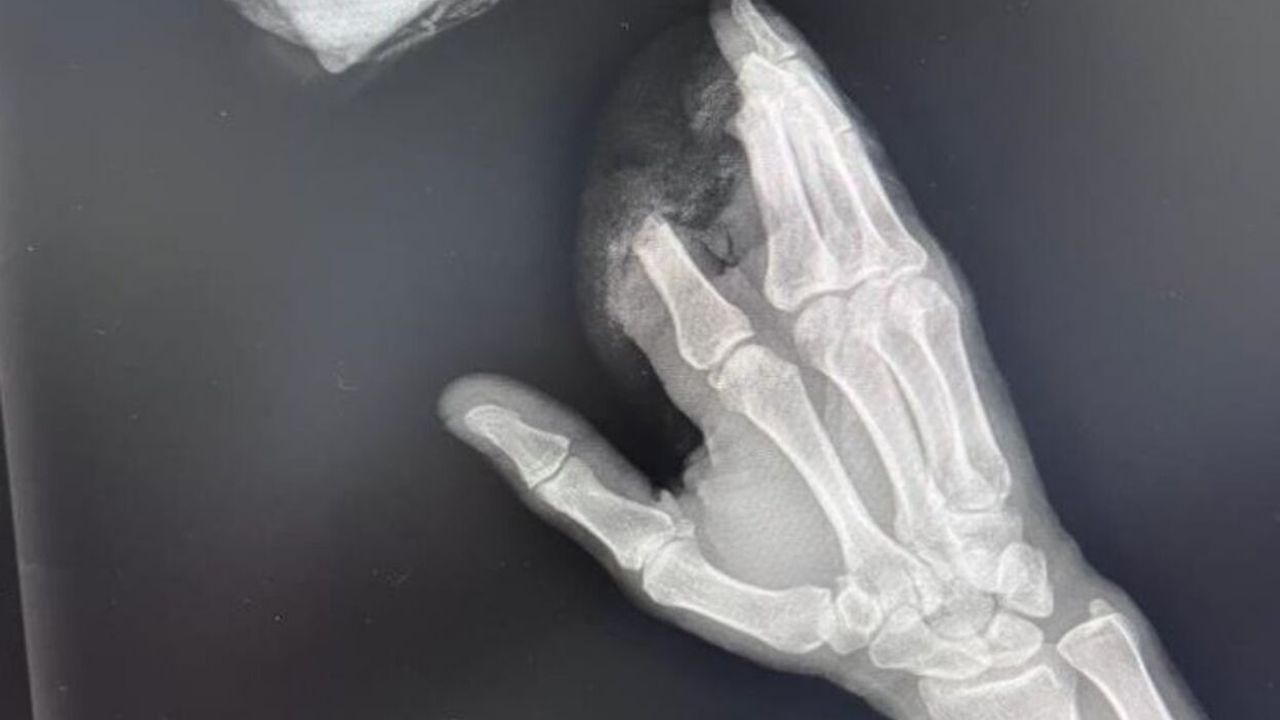

Ameliyatı gerçekleştiren ekipte bulunan Ortopedi ve Travmatoloji Anabilim Dalı Öğretim Üyesi Dr, Gökay Eker, "Hastamız iş kazası sonucu 3 parmağı kopmuş olarak bize geldi. Biz hastamızı bekletmeden acil bir şekilde ameliyata aldık. 12 saatlik süren bir operasyonla 3 parmağını yerine diktik. Burada mikro cerrahi tekniğini kullandık. Hastamızın parmakları şuan yaşıyor. takibine devam ediyoruz" şeklinde konuştu.